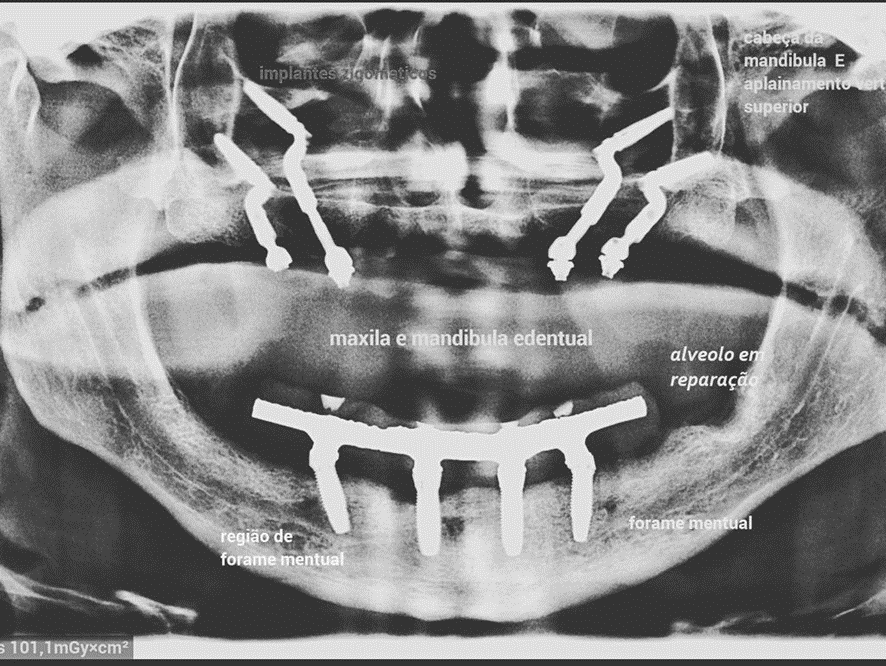

O Pilar Z é indicado como alternativa às Fixações Zigomáticas (FZ) para a reabilitação das maxilas extremamente atróficas. A técnica Facco dita que a ancoragem dos implantes no osso zigomático deve ser mais baixa em relação as FZ e se utiliza de implantes convencionais Due Cone de 13/15/17 mm X 3.5/4.0 mm, inseridos em plano paralelo ao longo eixo do zigoma. Portanto, menos invasiva e com riscos menores.

Caso 1 – Híbrido: dois Pilares Z e dois implantes convencionais

Caso 2 – Protocolo com quatro fixações

O posicionamento, junto ao rebordo alveolar, das plataformas dos Pilares Z, deverá ser aproximadamente próximo ao 16/26 para distais e próximo ao 12/21 para mesiais, configurando assim o polígono de Roy.